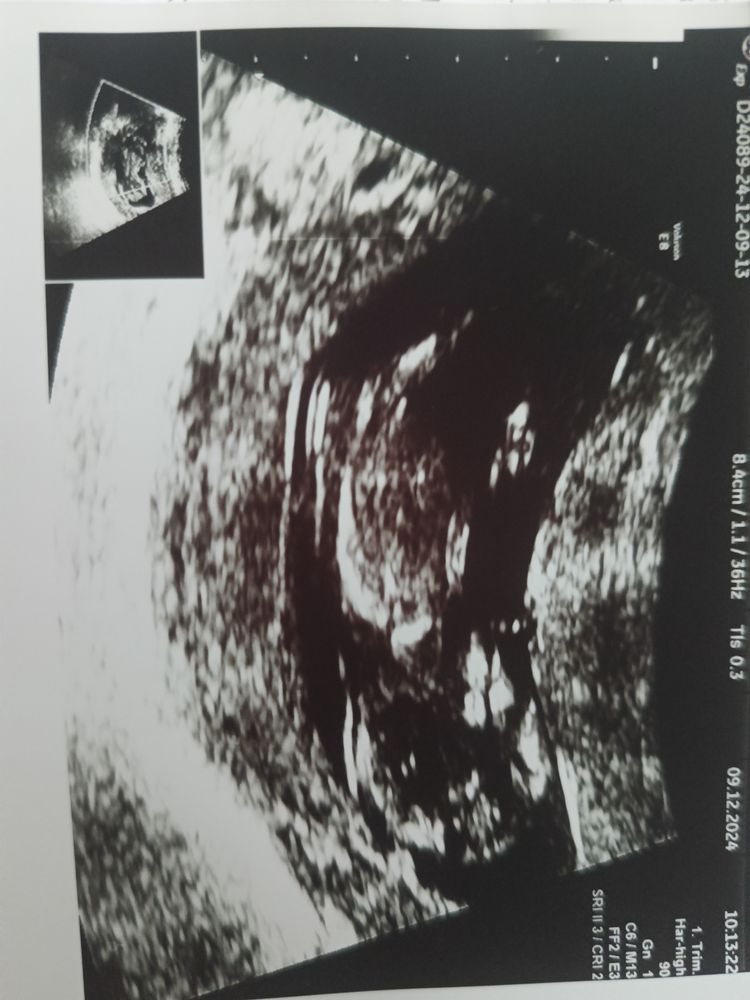

Фото с первого скрининга, на тот момент нам было 11 и 5. Хочется спросить: видите ли пол малыша? Но как видите бугорка нету😀 Просто оставлю здесь на память.